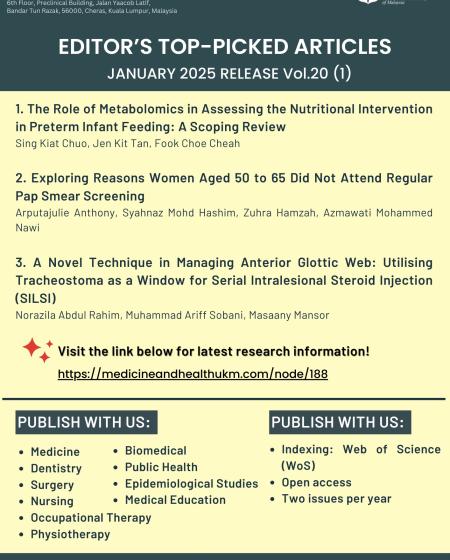

Benefit from a curated collection of peer-reviewed articles, providing reliable data and insights to support your research endeavors.Medicine and Health is an international open-access journal operated and published by the Faculty of Medicine, Universiti Kebangsaan Malaysia. The journal charges a standard article processing fee to the authors, while the readers can access all the articles published for free. The journal is published twice a year ( Jan and July) in electronic format. The journal publishes invited editorials, reviews, original research papers, interesting case reports and clinical quiz. All submitted manuscripts are subjected to a rigorous peer review process (single-blinded) by at least two independent reviewers in the specialised field. Articles are published in English language. In addition, an abstract in Bahasa Malaysia is also published for all the articles except editorials and clinical quiz.

| Type | Malaysian (MYR) | Non-Malaysian (USD) |

| Full Article / Review Article | 1,000 | 250 |

| Case Report / Brief Report | 500 | 125 |

| Editorial and/ Quizzes | No fee | No fee |